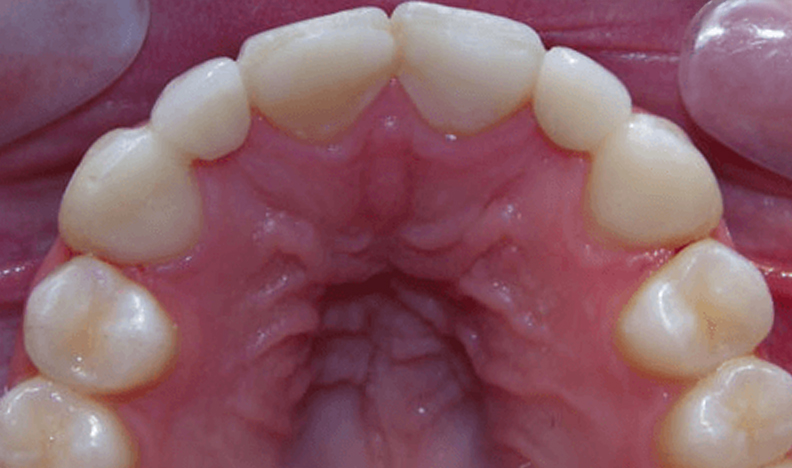

Ultimately, we chose to do two separate bridges out of an all-ceramic material, bonded only to the canines on each side. E.max lithium disilicate bridges from Ivoclar Vivadent 13-X and X-23, cemented by first air abrading the teeth, acid etching with Bisco’s Uni-etch 32% H3PO4 (aq) with BAC, and finally bonding in with Calibra Adhesive Resin cement as per recommended protocol. The results showcase a much more natural smile that’s both brighter and more resilient.